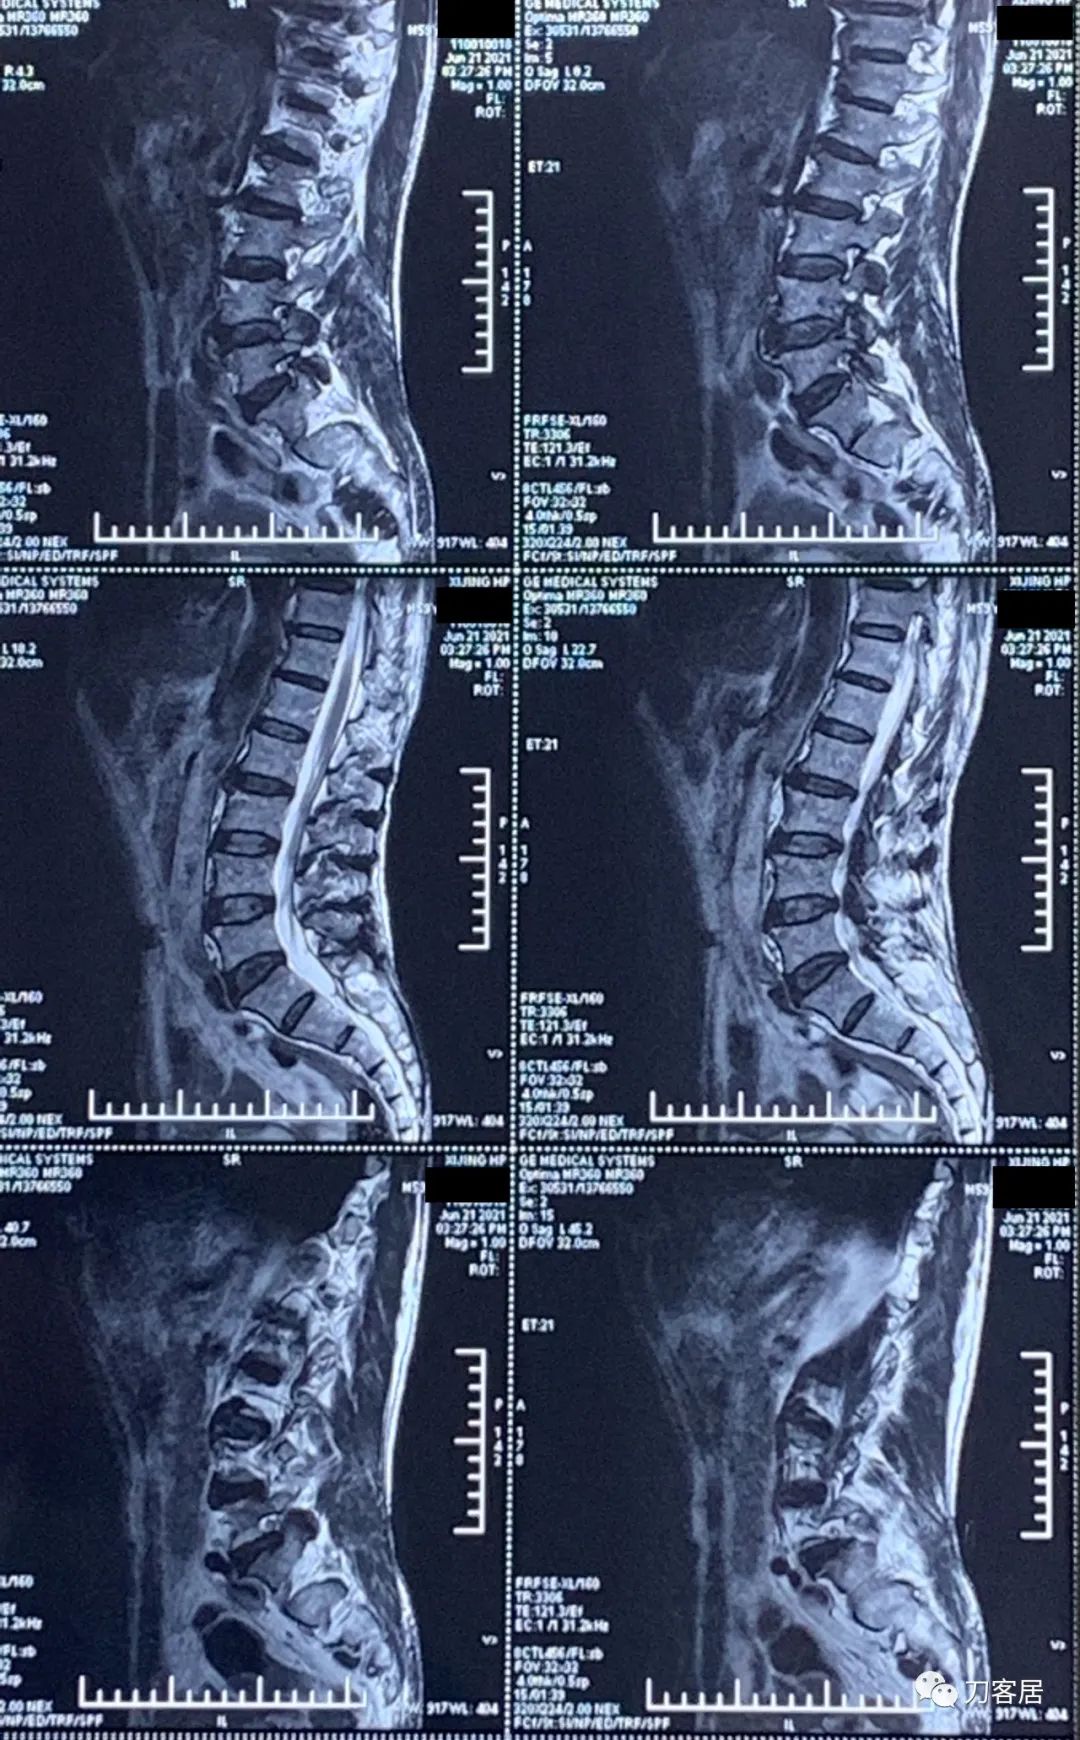

图3. 20210621西京医院腰椎MRI01

图4. 20210621西京医院腰椎MRI02